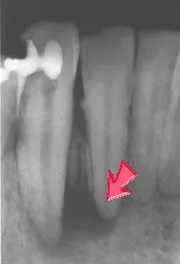

ウミの袋ができた状態

虫歯が酷くなると歯の内部にある神経(歯髄)を抜かなければならなくなり、さらに進行すると歯の根っこまで虫歯になり、その下にある歯茎の中に膿ができてしまうことがあります。

こうなってしまっては、通常の「削る、詰める」といった治療方法で治すことはできません。そこで行うのが根管治療です。専用の極細い器具を使用し、歯の根っこの管の中をきれいにお掃除していきます。